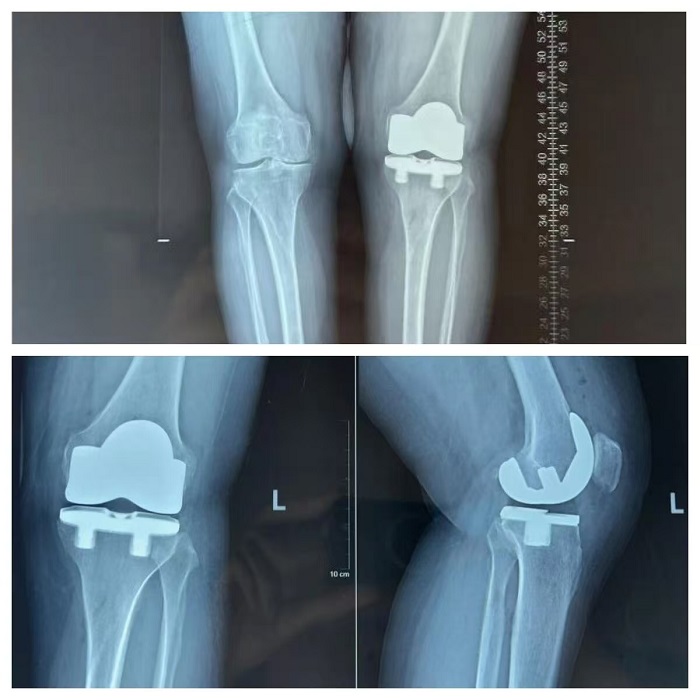

锡盟蒙医医院成功完成内蒙古首例生物膝关节置换术

近日,锡林郭勒盟蒙医医院关节外科成功完成了一项标志性手术,为一名因左膝关节疼痛8年余、近两年显著加重的48岁女性患者,实施了...